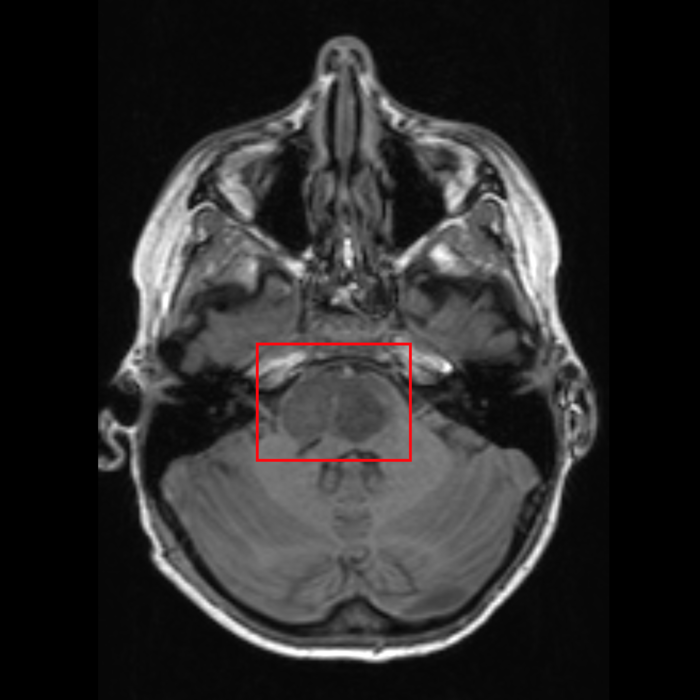

Asher’s MRI went as planned that morning, and before they brought him back to his hospital room, Leah and I were pulled into a consultation room with the neurosurgeon, an oncologist, and a couple of nurses. I don’t recall all of the exact words that were said. They explained the initial diagnosis, and filled in the rest as answers to our questions. We were told that the tumor in Asher’s brain is called a diffuse intrinsic pontine glioma (DIPG). Tje diffuse nature of the tumor means the bad cells are mixed in with healthy cells, so it cannot be removed surgically. It is located in the pons of the brain, which controls the major functions of the body that keep us alive like breathing and heart rate, making it risky to operate on. DIPG tumors are typically aggressive to the point of being considered stage four. The standard of treatment is radiation therapy, which he will need to receive at St. Jude’s Children’s Research Hospital in Memphis. There are clinical trial options available. We had to decide whether or not for them to perform a biopsy, the first of many medical decisions we would need to make along the way.

By the time I had returned to the hospital, someone had already spent some time with Asher, showing him a picture of the tumor in his MRI. In true Asher form, he had already named his DIPG tumor “Dippy,” and loved to point out that it was “shaped like a butt.”